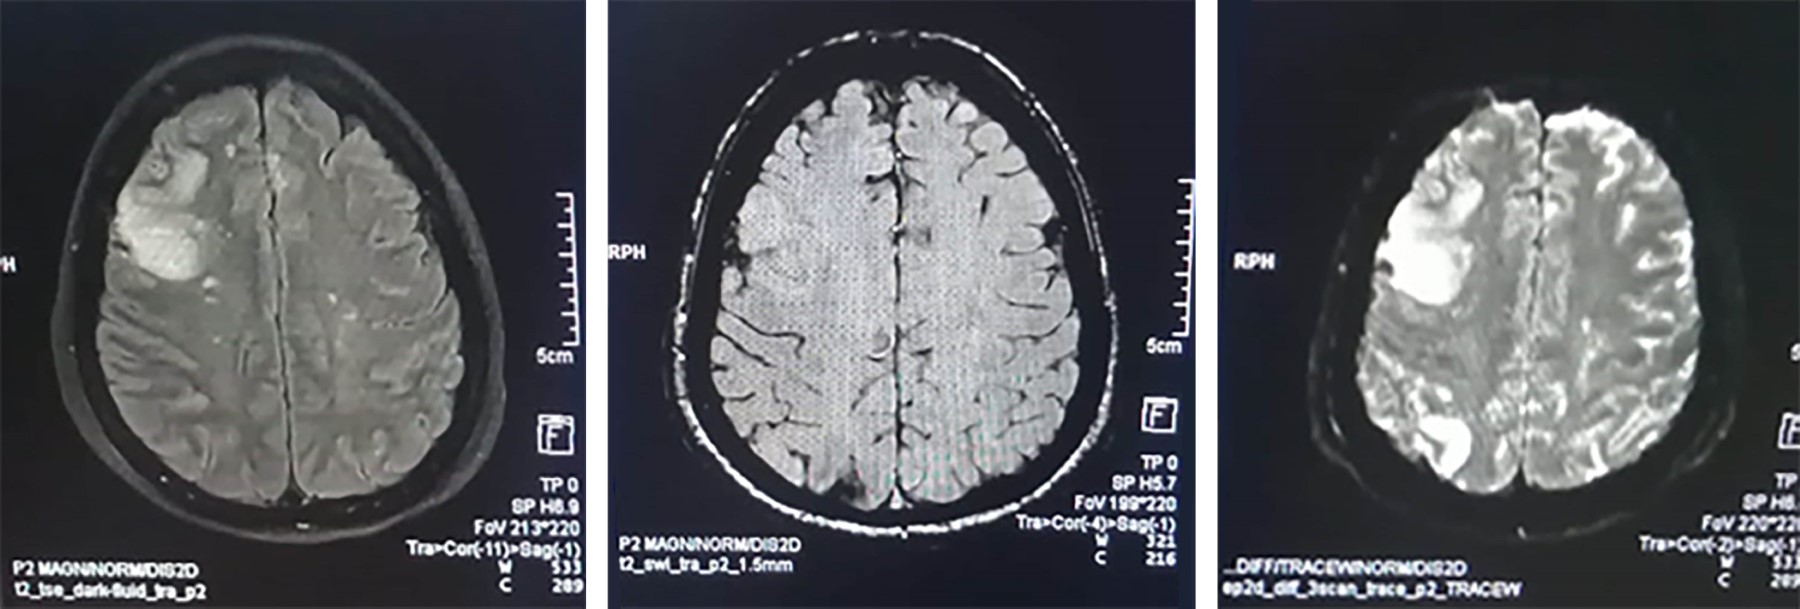

Durante las primeras 48 horas de estancia la paciente presenta deterioro neurológico con descenso de dos puntos en la escala de Glasgow. Además, en la vigilancia y neuromonitoreo con ultrasonido Doppler transcraneal se evidenció, a nivel de la arteria cerebral media de lado derecho: velocidad sistólica 169 cm/s, diastólica 78 cm/s con índice de pulsatilidad (IP) de 0.7 cm/seg, diámetro de la vaina del nervio óptico de lado derecho 0.6 mm; y en arteria cerebral media de lado izquierdo: velocidad sistólica de 212 cm/s, diastólica 96 cm/s con IP 0.7 mm y vaina del nervio óptico de lado izquierdo 0.36 mm. Se integra el diagnóstico probable de vasoespasmo leve con velocidad media de la arteria cerebral de lado izquierdo de 131 cm/seg. Se ajusta tratamiento con nimodipino (Figura 1).

Figura 1